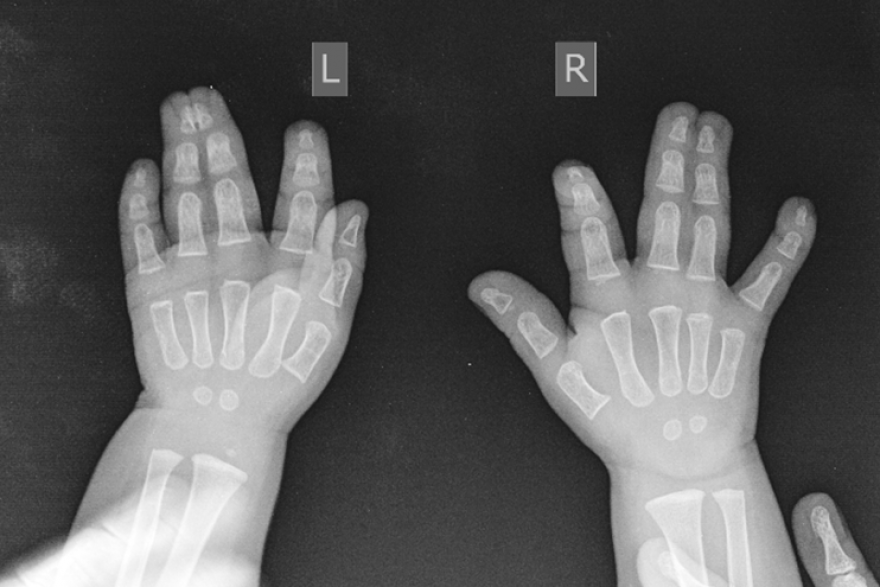

Микрохирурги Центра Илизарова устранили у годовалого пациента из Тюменской области врожденную аномалию обеих кистей.

Специалисты центра сообщили, у полуторагодовалого малыша полная кожная синдактилия III-IV пальцев правой кисти, кожно-костная синдактилия III-IV пальцев левой кисти - сросшиеся пальчики. Для лечения микрохирурги используют методики, которые разработали врачи Центра на основе открытия Илизарова, и его аппарат для остеосинтеза трубчатых костей кисти.

- Методика включает 2 этапа: первый этап – наложение аппарата Илизарова для создания запаса мягких тканей. Мы начинаем выращивать кожу для формирования межпальцевых промежутков. После этого разделяем пальцы, а появившийся раневой дефект закрываем выращенной кожей. Благодаря данной методике отсутствует необходимость брать кожу с донорских участков, - объясняет суть методики заведующий травматолого-ортопедическим отделением №13 НМИЦ ТО имени акад. Г.А.Илизарова Минздрава России   Денис Тягунов.

Первый этап лечения для малыша завершился. Отдельные пальцы сформированы на одной руке. Сейчас врачи начали аналогичным методом работать над сросшимися пальчиками на второй кисти.